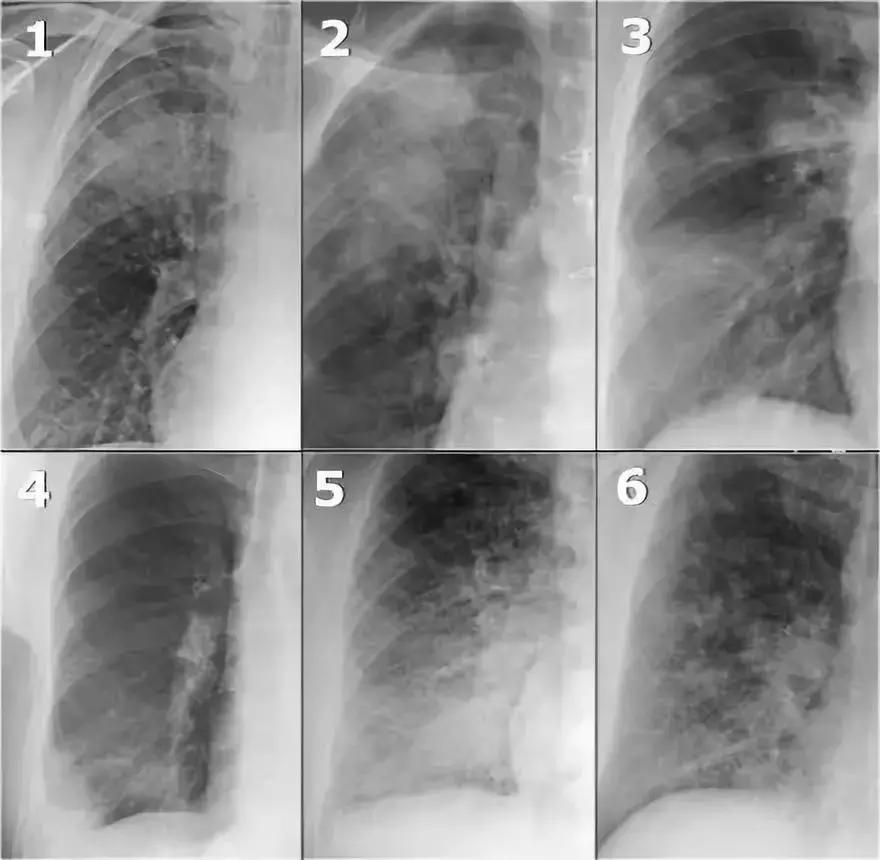

(2)病例

通过胸部X线,能发现什么,鉴别诊断是什么?

图14 多灶性实性病变

分析:

➢ 双肺多发阴影

➢ 右下肺边界模糊,阴影较大,可能存在空气-支气管征

➢ 可能会按照多灶性实变处理,同时需要考虑多发模糊团块的可能

➢ 呈现外周分布

➢ 患者无痰咳嗽数月,抗菌药物治疗无效。

➢ 在慢性实变范围内进行鉴别诊断

➢ 支气管肺泡癌和淋巴瘤癌的实验室检测指标正常

➢ 无嗜酸粒细胞增多症,排除嗜酸性粒细胞肺炎的可能

活检结果显示:机化性肺炎(OP)

图15 机化性肺炎(OP)